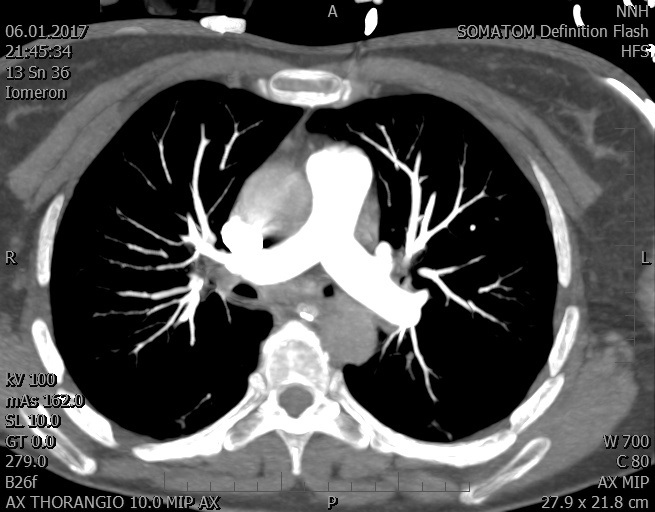

Video 2 - Echokardiograficky byla zjištěna těžká dysfunkce dilatační levé komory s nezvětšenou pravou komorou.Pro nejasnou příčinu zástavy jsme provedli i vyšetření výpočetní tomografií (CT), které vyloučilo plicní embolizaci (série 1 - soubory na konci článku). V den přijetí při přetrvávající oběhové nestabilitě byla nemocná opakovaně defibrilována pro fibrilaci komor se stabilizací rytmu po podání amiodaronu a mesocainu. Dle hemodynamických měření se jednalo o těžký kombinovaný šok. Vstupní laboratorní vyšetření bylo bez větších pozoruhodností. Posléze jsme doplnili anamnézu od příbuzných a zjistili, že pacientka užila do dvou hodin před srdeční zástavou první tabletu amoxicilinu na lehký respirační infekt. Při nevýtěžnosti vstupních vyšetření a nových anamnestických informacích jsme doplnili 14 hodin po kolapsu vyšetření koncentrace tryptázy v séru, která byla extrémně zvýšena (tabulka 2), což nás vedlo k podezření na anafylaxi.